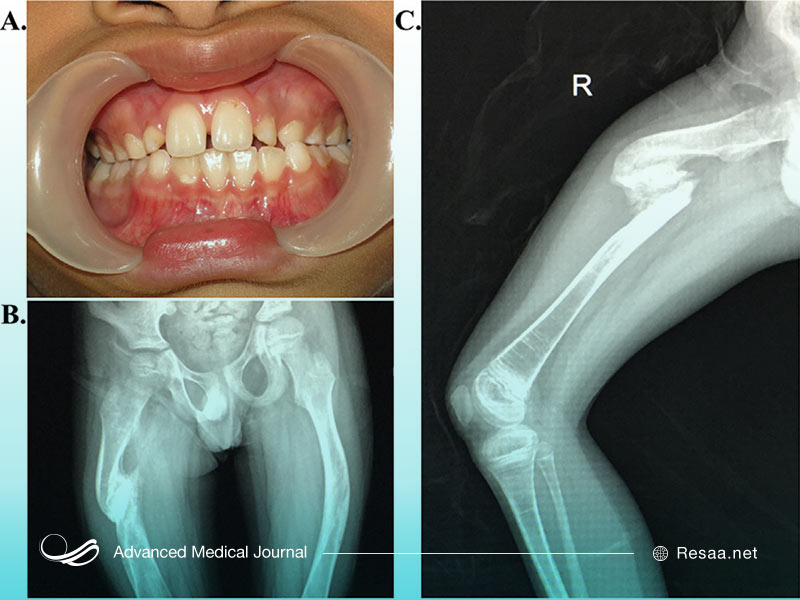

نوع 1 OI خفیفترین و رایجترین نوع بیماری شکنندگی استخوان است. در این نوع بیماری شکنندگی استخوان، بدن شما کلاژن با کیفیت خوب تولید میکند اما مقدار کافی از آن را تولید نمیکند. این وضعیت منجر به بروز استخوانهای شکننده با درجه خفیف میگردد. به طور معمول کودکان مبتلا به OI نوع 1 به دلیل ضربههای خفیف دچار شکستگی استخوان میشوند. چنین شکستگیهای استخوانی در بزرگسالان بسیار کمتر مشاهده میشود. این احتمال وجود دارد که دندانها نیز تحت تأثیر قرار بگیرند، در نتیجه ترک و حفره دندان ایجاد میشود.

معرفی نوع 4 OI

نوع 4 OI متغیرترین شکل بیماری شکنندگی استخوان است زیرا علائم آن از خفیف تا شدید متغیر است. همانند نوع 3 OI، بدن شما به اندازه کافی کلاژن تولید میکند اما کیفیت بسیار پایین است. به طور معمول کودکان مبتلا به OI نوع 4 با پاهای خمیده متولد میشوند، گرچه با افزایش سن این خمیدگی کاهش مییابد.

بیماری شکنندگی استخوان دارای یک یا چند مورد از علائم زیر است:

- دندانهای ضعیف

- مشکلات مربوط به تشکیل دندان (دندانپزشکی یا DI)

به طور معمول تصویربرداری مانند اشعه ایکس برای بررسی شکستگی و تغییرات استخوان پیشنهاد میشود. اسکن تراکم استخوان (DEXA) میتواند در کودکان با وزن بیش از 10 کیلوگرم انجام شود اما اطلاعات کافی برای ارائه نتایج دقیق در کودکان زیر پنج سال در دسترس نیست. آزمایش ژنتیک امکانپذیر است اما به طور معمول انجام نمیگردد. همچنان OI یک تشخیص بالینی است.

پزشک میتواند با استفاده از اشعه ایکس بیماری شکنندگی استخوان را تشخیص دهد. اشعه ایکس به پزشک اجازه میدهد استخوانهای شکسته فعلی و قدیمی را ببیند. همچنین این روش، مشاهده نقص در استخوانها را برای آنها آسان میکند. از آزمون آزمایشگاهی ممکن است به منظور تجزیه و تحلیل ساختار کلاژن کودک شما استفاده شود. در برخی موارد ممکن است پزشک شما بخواهد بیوپسی با پانچ پوست “skin punch biopsy” انجام دهد. در طی این نمونه برداری، پزشک از یک لوله توخالی و تیز استفاده میکند تا نمونه کوچکی از بافت شما را بردارد.